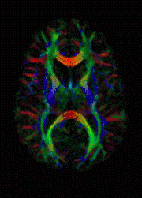

![]() DTI Color Map | |

The imaging of this property is an extension of diffusion MRI. If a series of diffusion gradients (i.e. magnetic field variations in the MRI magnet) are applied that can determine at least 3 directional vectors (use of 6 different gradients is the minimum and additional gradients improve the accuracy for "off-diagonal" information), it is possible to calculate, for each voxel, a tensor (i.e. a symmetric positive definite 3×3 matrix) that describes the 3-dimensional shape of diffusion. The fiber direction is indicated by the tensor's main eigenvector. This vector can be color-coded, yielding a cartography of the tracts' position and direction (red for left-right, blue for superior-inferior, and green for anterior-posterior).[45] The brightness is weighted by the fractional anisotropy which is a scalar measure of the degree of anisotropy in a given voxel. Mean diffusivity (MD) or trace is a scalar measure of the total diffusion within a voxel. These measures are commonly used clinically to localize white matter lesions that do not show up on other forms of clinical MRI.[46]